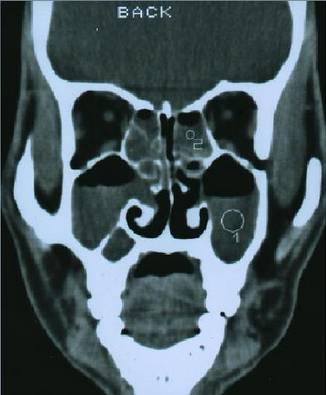

(二)检查

1、内镜检查:来源于中鼻道、嗅裂的黏脓性分泌物,中鼻道粘膜充血、水肿或有鼻息肉。

2、影像学检查:CT扫描显示窦口鼻道复合体或鼻窦粘膜病变。

• 副鼻窦X线检查,CT(冠状位、轴位)检查已常规应用。

正常鼻窦CT

鼻窦炎冠状CT